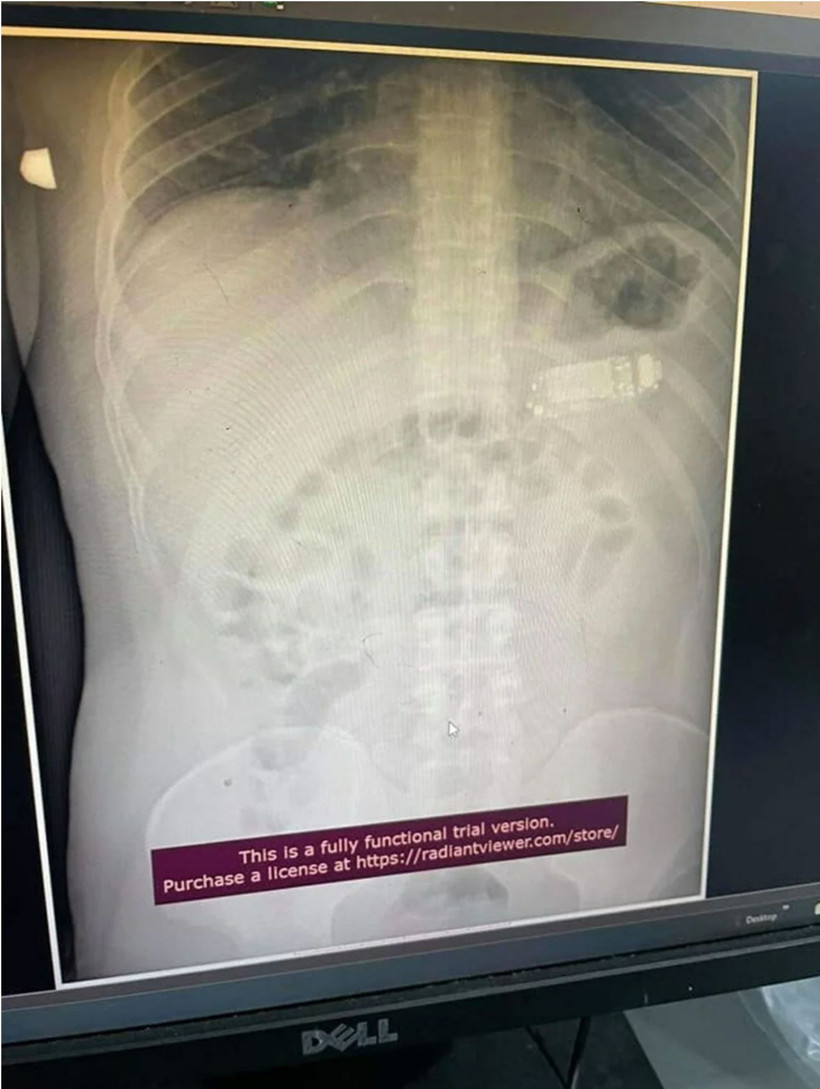

Kosova'nın başkenti Piriştine'de ilginç bir olay yaşandı. Doktorlar 33 yaşındaki bir erkek hastanın midesinden, Nokia 3310'unun yenilenmiş versiyonunu ameliyatla çıkardı. Uzmanlar, özellikle telefonunun bataryasından kaynaklanan kimyasalların yutulması durumunda ölümcül olacağını vurguladı.

Midesinde 4 gün kaldı

Güneydoğu Avrupa'da denize kıyısı olmayan bir ülke olan Kosova'nın başkenti Priştine'de doktorlar, Nokia 3310 model bir cep telefonunu yutan adamı ameliyat etti. Telefonun adı açıklamayan adamın midesinde dört gün kaldığı belirtildi. Başarılı operasyonu gerçekleştiren sağlık ekibinin başındaki doktor Skender Teljaku, adamın midesinden çıkarılan telefonun fotoğrafları ile röntgen ve endoskop görüntülerini Facebook'ta yayınladı.

Teljaku yaptığı açıklamada, tıbbi ekibin telefonu mideyi kesmeden, endoskop olarak bilinen özel cihazlar kullanarak üç ayrı parçaya ayırmayı başardığını söyledi. Teljaku, ayrıca yaklaşık iki saat süren işlem sırasında "herhangi bir komplikasyon" yaşanmadığını sözlerine ekledi.

Bununla birlikte 33 yaşındaki  adamın telefonu yuttuktan sonra yaşadığı acı nedeniyle Kosova'nın başkentindeki hastaneye gitmeye karar verdiği aktarıldı. Teljaku, özellikle bataryanın en tehlikeli parçası olduğunu, patlayarak hayatı potansiyel olarak tehlikede olan adamın bağırsaklarına kimyasal salabileceğini söyledi.